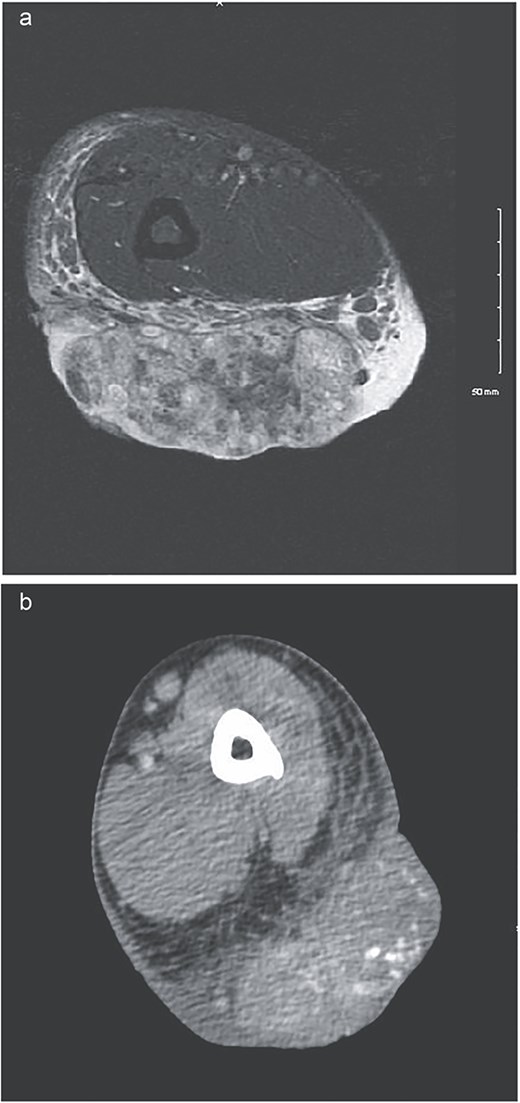

Left lateral elbow soft tissue mass, measures 11.5 × 9.5 × 4 cm.

(a) MRI showing low signal on T1 and heterogeneously increased in signal on T2 sequences. Extensive surrounding subcutaneous edema with involvement of the dermal layer, as well as mild edema along the anterior fascia of the muscle. No definitive involvement of the muscle compartments noted, no involvement of neurovascular bundle. Some enlarged epitrochlear lymph nodes seen within the medial aspect of the elbow, with concern for possible local metastatic disease. (b) CT upper extremity demonstrating calcified arm lesion with vascularity supplied from branches of the proximal brachial artery. Involvement in the dermis and subdermal fat.